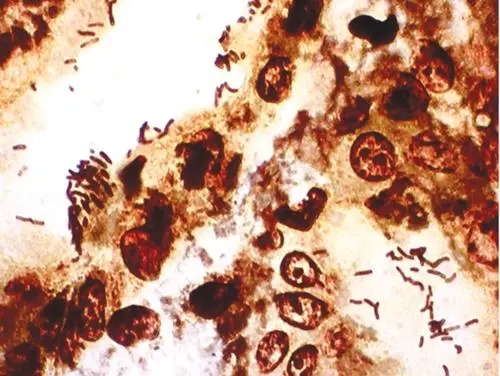

番紅o染色

番紅o染色:番紅(也稱作番紅O或基本紅2)是個用在組織學和細胞學的生物染色劑。番紅在一些染色的實驗計劃表中用作復染劑,將所有的細胞核染成紅色。這在革蘭氏染色和內孢子染色都是典型的復染劑。它也可以被用

番紅o染色:番紅(也稱作番紅O或基本紅2)是個用在組織學和細胞學的生物染色劑。番紅在一些染色的實驗計劃表中用作復染劑,將所有的細胞核染成紅色。這在革蘭氏染色和內孢子染色都是典型的復染劑。它也可以被用來檢測軟骨、黏蛋白和肥大細胞的顆粒。